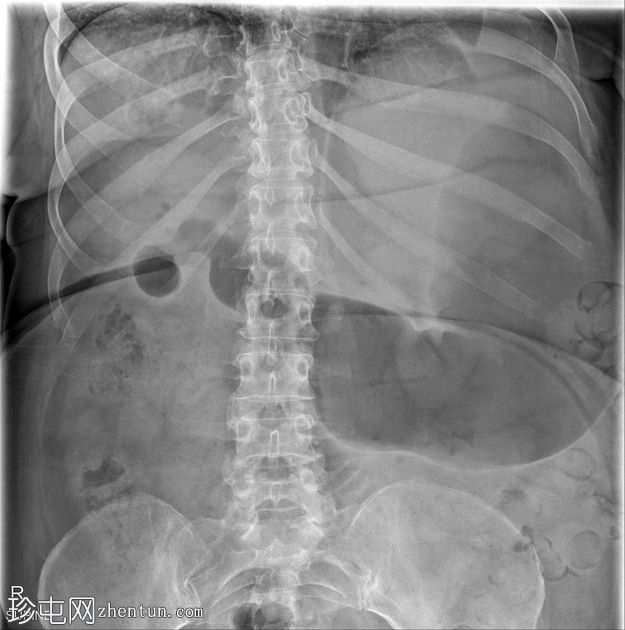

CT

冠状位增强扫描(门静脉期)

胆结石引起的高度小肠梗阻(胆结石性肠麻痹)

胆结石已侵蚀穿过胆囊壁进入十二指肠,形成胆囊十二指肠瘘

胆囊壁增厚,胆囊周围脂肪浸润,符合并发胆囊炎的影像学表现。胆囊窝内可见游离气体,但其他部位未见游离气体

胆囊颈或胆囊管内嵌顿胆结石

偶然发现的肠旋转不全